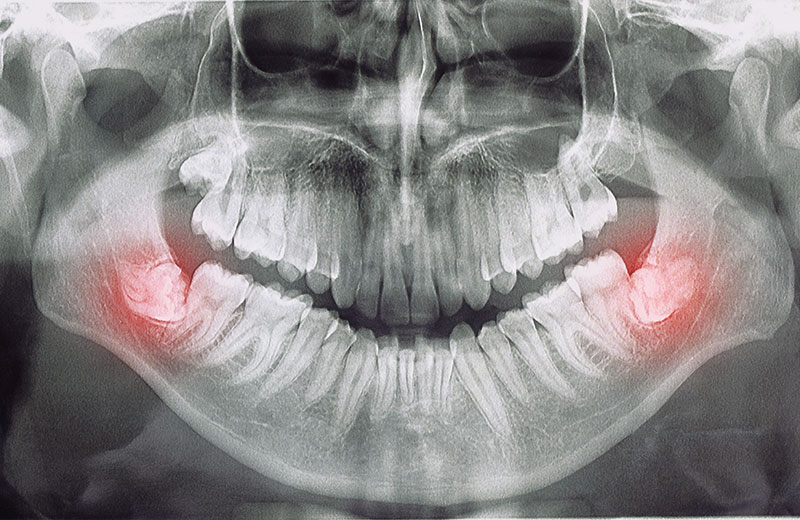

20’lik dişler, diğer adıyla üçüncü azı dişleri, genellikle 17–25 yaş aralığında sürmeye başlayan son kalıcı dişlerdir. Ağızda yeterli yer bulunmadığında bu dişler yarı gömülü ya da tam gömülü şekilde çıkabilir. Bu durum diş eti iltihaplarına, çene ağrılarına veya diş diziliminde bozulmalara neden olabilir.

Dişin konumu ve çevre dokular üzerindeki etkisi, panoramik röntgen görüntüsüyle değerlendirilir.